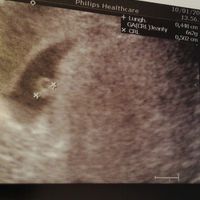

Ho caricato una foto nel post di Maria